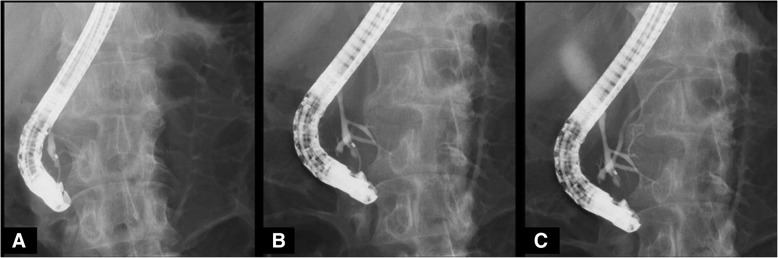

A 67-year-old man was found to have a dilatation of the common bile duct (CBD) (19 mm) during a medical examination at 62 years of age. The dilatation of the CBD subsequently progressed (26 mm), and he was admitted to our hospital for surgical treatment. Abdominal computed tomography revealed a dilatation of the CBD with no tumor or stone. Magnetic resonance cholangiopancreatography revealed a dilatation from the common hepatic duct (CHD) to the middle bile duct (Fig. 1a and b) with PBM (Fig. 1c). Endoscopic retrograde cholangiopancreatography (ERCP) from the papilla of Vater revealed the pancreatic main duct via the pancreatic branch duct (Fig. 2a and b). PBM with dilatation of the CBD (26 mm) and incomplete PD were revealed (Fig. 2c). Figure 3 shows a schema of this case with dilatation of the CBD and PBM, and incomplete PD in which the ventral pancreatic duct joined the dorsal pancreatic branch duct was observed.

We planned an extrahepatic bile duct resection and hepaticojejunostomy because of high risk of malignant transformation. Laparotomy was performed by a right hypochondrium incision. Taping and transection of the bile duct without dilatation on the pancreatic side were performed, and thereafter, two orifices of the common channel and ventral pancreatic duct were ligated (Fig. 3). The transection line of the CHD without dilatation was identified using cholangiography (Fig. 3), and then, the CBD was resected. The level of amylase in the bile was 7217 IU/L, and a histological examination of the CBD showed an inflammatory change of CBD, not a malignant transformation.